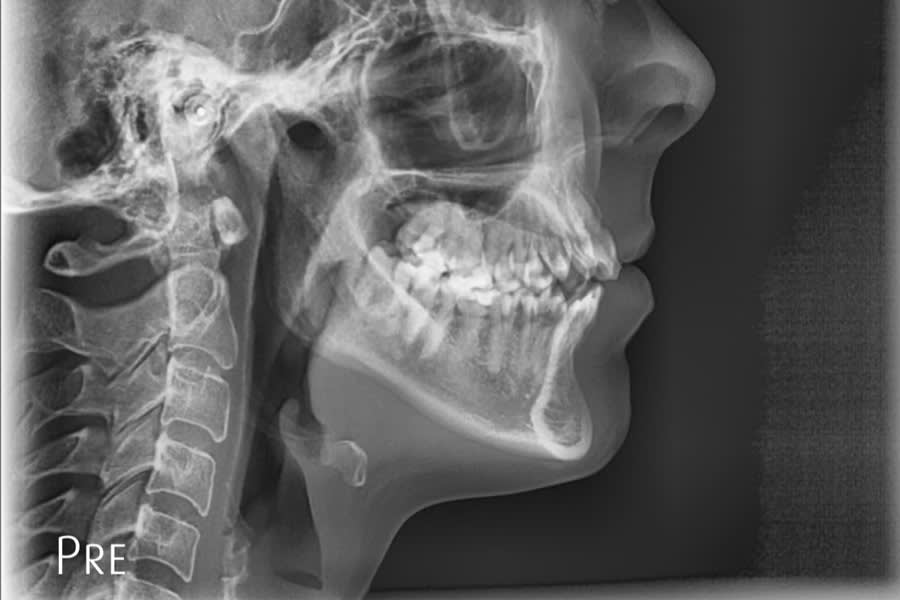

A 31-year-old female patient presented with the following intraoral conditions: an anterior open bite, bimaxillary crowding, negative crown torque, early “black triangles,” and a thin phenotype/biotype with early recessions. Her extraoral situation included a gummy smile with high-lip mobility, asymmetric arch forms and posterior corridors, and incompetent lip closure (Figure 2 through Figure 4). Collectively, these factors increase esthetic and periodontal risk and favor posterior intrusion over anterior intrusion.4-8,12-16

Radiographic Follow-up

Panoramic/cephalometric re-evaluation is used to document posterior intrusion without root resorption or sinus compromise, improved upper incisor angulation in bone, lip profile changes consistent with CCW autorotation, and favorable skeletal parameters.7,17-21 (Figure 18 through Figure 21)